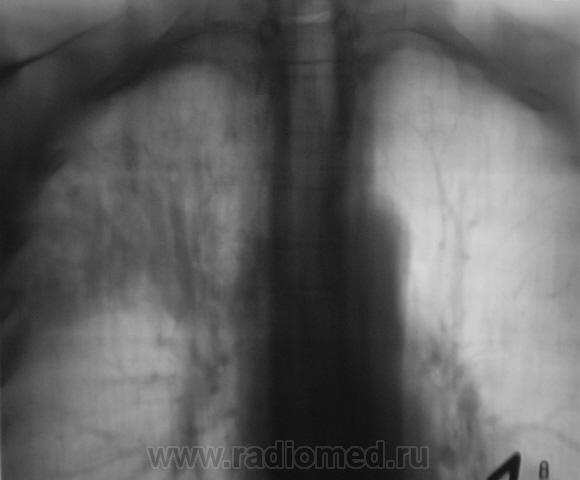

Пациент, при расшифровке флюорограмм, "взят на контроль". Произведено стандартное рентгенологическое исследование. Вот рентгенограмма.

Томограммы.

Ваше мнение уважаемые коллеги?